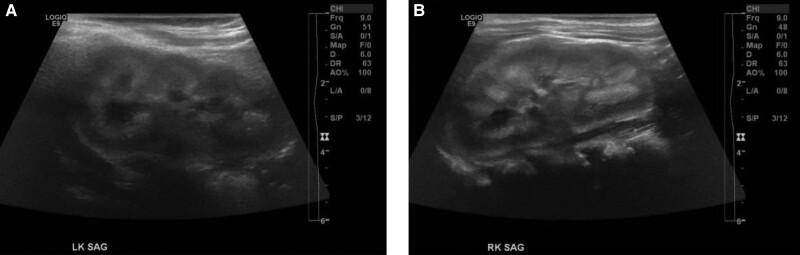

一名此前健康的11个月大足月女婴,从10个月大开始出现生长发育迟缓、喂养不耐受和易激惹。她的血清钙水平为3.75 mmol/L(15 mg/dL)(参考范围为2.13 - 2.62 mmol/L;8.5 - 10.5 mg/dL),符合严重高钙血症。她有双侧肾钙质沉着症。通过静脉补液,高钙血症有所改善,但一旦停止静脉补液并采用低钙饮食,钙水平又再次升高。针对高钙血症常见病因的实验室检查均为阴性。粪便还原物质检测有两次呈阳性。内镜活检证实双糖酶水平较低。她的饮食改为不含双糖的配方奶,高钙血症得以缓解。先天性双糖酶缺乏症的基因检测结果为阴性。在重复内镜检查显示双糖酶水平有所改善后,双糖逐渐重新引入饮食中,钙水平仍保持正常。该病例表明,双糖酶缺乏症这种与高钙血症相关的罕见先天性代谢缺陷,可能是高钙血症的一个短暂病因。高钙血症的机制尚不清楚。